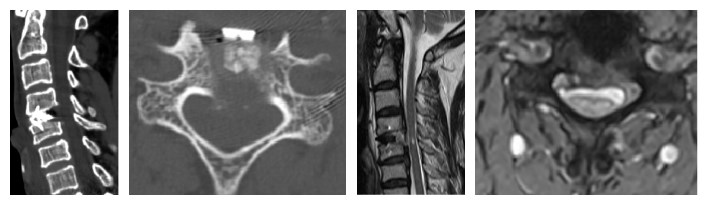

術(shù)后復(fù)查CT及MRI提示患者原頸4/5突出的椎間盤及骨化的后縱韌帶已被去除,腦脊液流通暢順,椎管狹窄得到解除。